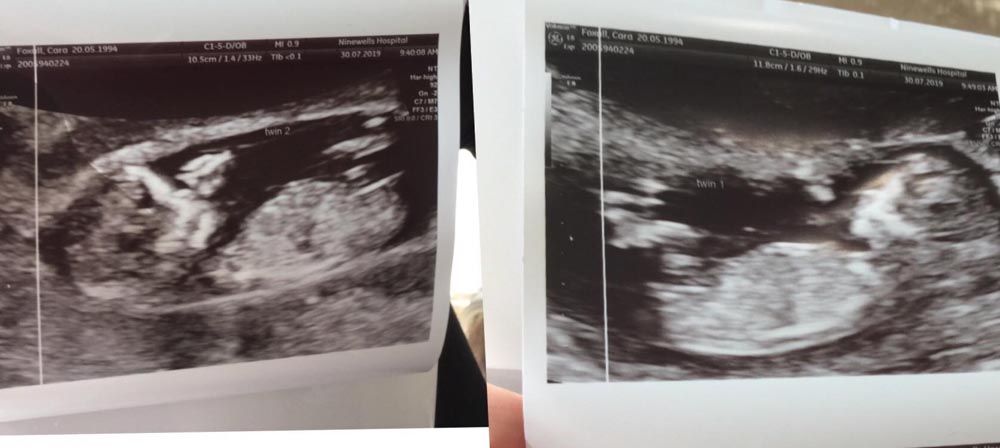

Now, as Cara prepares to welcome her new babies – due in January 2020 – into the world, she has also defended her decision to have children with an older man.